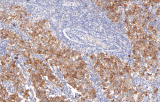

La inmunohistoquímica (IHQ) se ha convertido en un componente esencial de la patología genitourinaria (GU) moderna, permitiendo la caracterización precisa de tumores que afectan a la próstata, riñón, vejiga urinaria y testículo. La literatura revisada por pares destaca consistentemente que la morfología sola puede ser insuficiente en biopsias difíciles o muestras de tejido limitadas; por lo tanto, los paneles de IHQ basados en anticuerpos desempeñan un papel central en el diagnóstico diferencial, la clasificación tumoral y la toma de decisiones clínicas guiadas por biomarcadores.

Alta especificidad y sensibilidad diagnóstica

Los datos revisados por pares demuestran que los marcadores de anticuerpos seleccionados proporcionan una fuerte discriminación diagnóstica, mejorando la precisión en casos difíciles donde la histología rutinaria sola puede ser inconclusa.